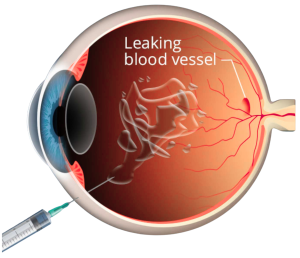

Diabetic retinopathy is a diabetes-related eye condition that affects the retina, the light sensitive layer at the back of the eye, that plays a vital role in vision. It develops when prolonged high blood sugar levels damage the small blood vessels that supply oxygen and nutrients to the retina.

This is the earlier stage of the condition where small blood vessels in the retina weaken or leak small amounts of fluid, but many patients do not experience noticeable vision changes as symptoms are often absent at this stage. Regular eye examinations play an important role in early detection and allows timely intervention to prevent further progression. - Proliferative Diabetic Retinopathy (PDR)

This is a more advanced stage of the disease. When blood supply to the retina is reduced, the eye responds by growing new abnormal blood vessels. These vessels are fragile and bleed more easily, increasing the risk of more severe vision problems such as vitreous haemorrhage, membranes and traction on the retina, retinal detachment, or even high eye pressures.

When leakage occurs from the retinal blood vessels located in the central part of the retina, i.e. the macula, fluid accumulates amongst the important light-sensing cells responsible for fine and precise vision. This causes vision to become blurry or distorted.

The primary cause of diabetic retinopathy is long-term exposure to high blood sugar levels. Over time, excess glucose damages the retinal blood vessels, affecting their ability to function properly. This causes leakage and bleeding into the retina.

- Intravitreal Injections of Anti-VEGF or Sustained-Release Steroid Implants

Medications are delivered through eye injections to reduce retinal swelling and control abnormal blood vessel growth. These treatments are commonly used in moderate to advanced cases.